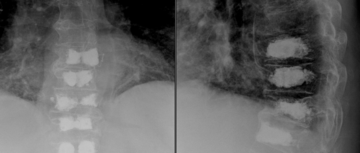

Kyphoplastie mehrerer Brustwirbelkörper bei Brüchen der Brustwirbelsäule (Multiples Myelom).